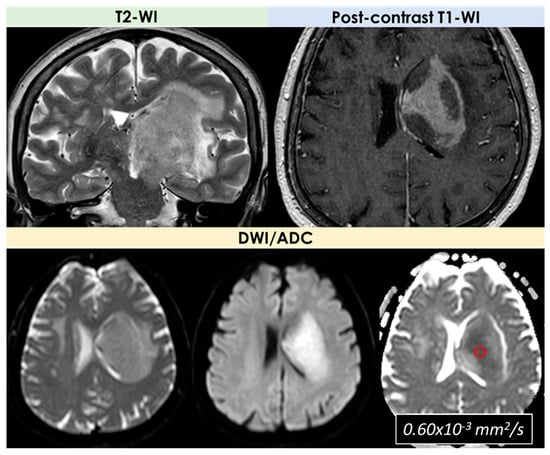

- Signal features: T1-Weighted Imaging (T1-WI) hypointense signal and intermediate to hyperintense signal on T2WI without diffusion restriction; intralesional microhemorrhages (small linear or punctate patterns on either Gradient Recalled Echo (GRE-T2*) or Susceptibility Weighted Imaging (SWI)) in 8/10 (80%) patients;

| DWI/ADC | Hyperintense on DWI/hypointense on ADC maps Decreased FA values in lesions | High ADC values in center of lesion and relatively low ADC values in periphery of lesion Threshold for the minimum ADC value for distinguishing TDLs from PCNSL is 0.556 × 10−3 mm2/s | Hypointense in DWI and ADC | Hypointense on DWI and ADC | “Eccentric target sign” consisting of an eccentric nodule along the rim of an enhancing lesion on T1-WI ADC > 1.6 × 10−3 mm2/s suggestive of toxoplasmosis |